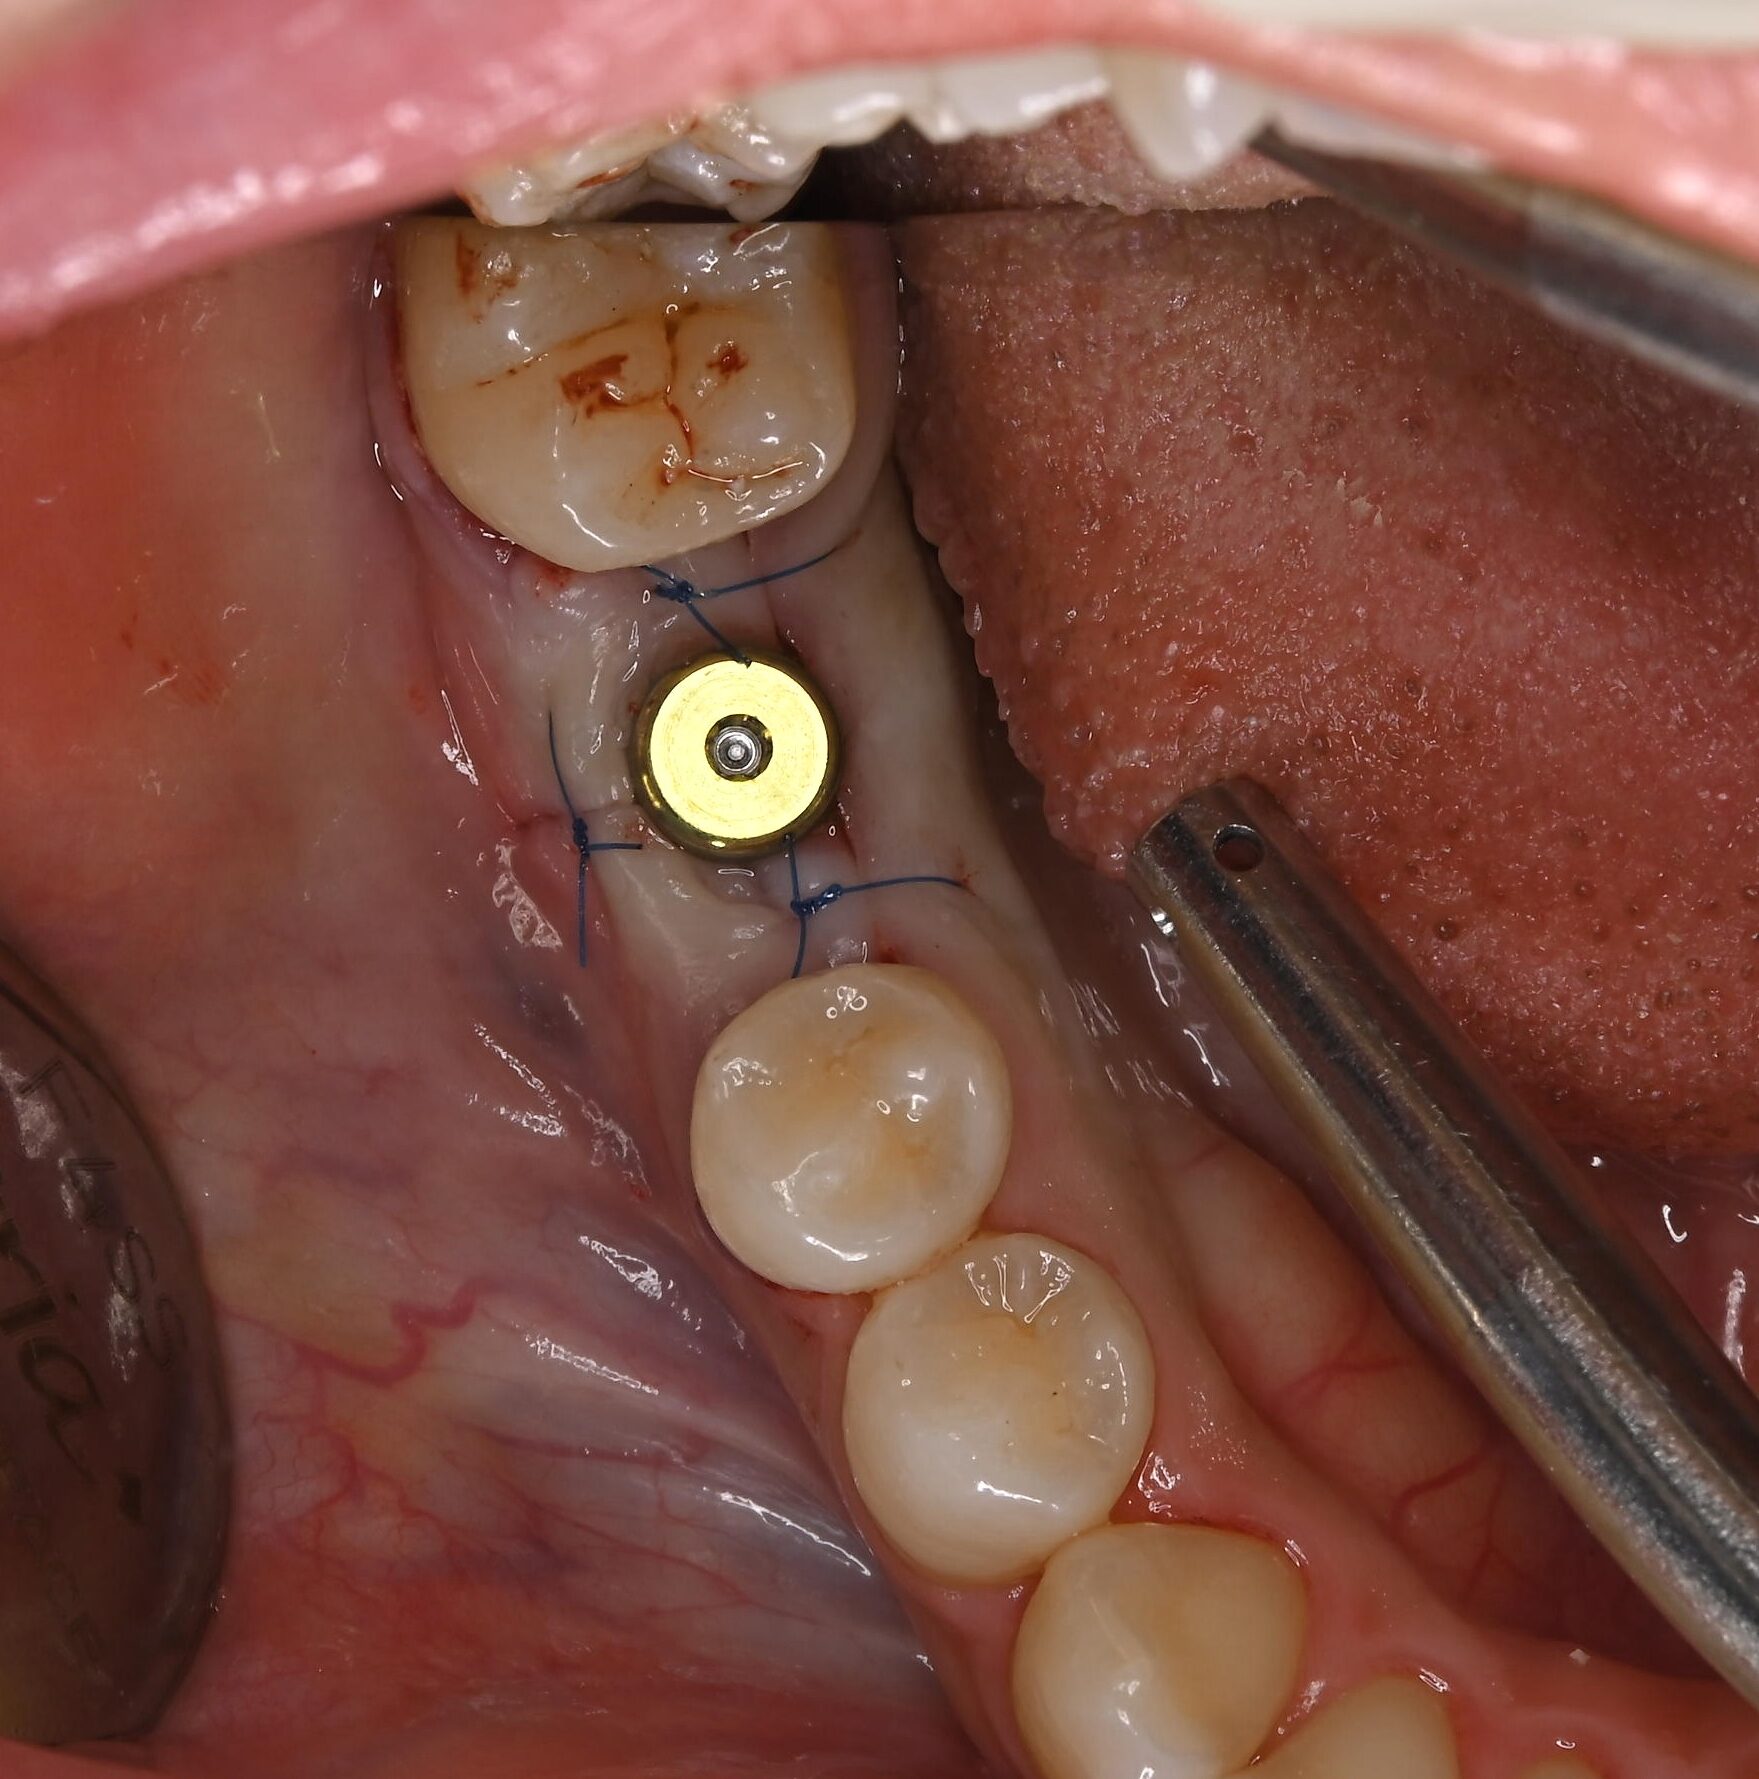

右下奥歯のインプラント症例

Before

• 右下6番欠損です。

• インプラントを埋入するのと同時にヒーリングキャップを取り付けました。

After

治療内容

右下の奥歯を根の先の膿が原因で抜歯された患者様です。

ブリッジ治療では両隣の歯を大きく削らないといけない為、インプラント治療を希望されました。

骨の治り方が歪で、頬側の骨が大きく足りないため骨造成を行い、インプラントを埋入した日にヒーリングキャップを装着し、インプラントが骨と結合するまで待ちます。

その後、型取りをし被せ物をスクリューにて装着しています。